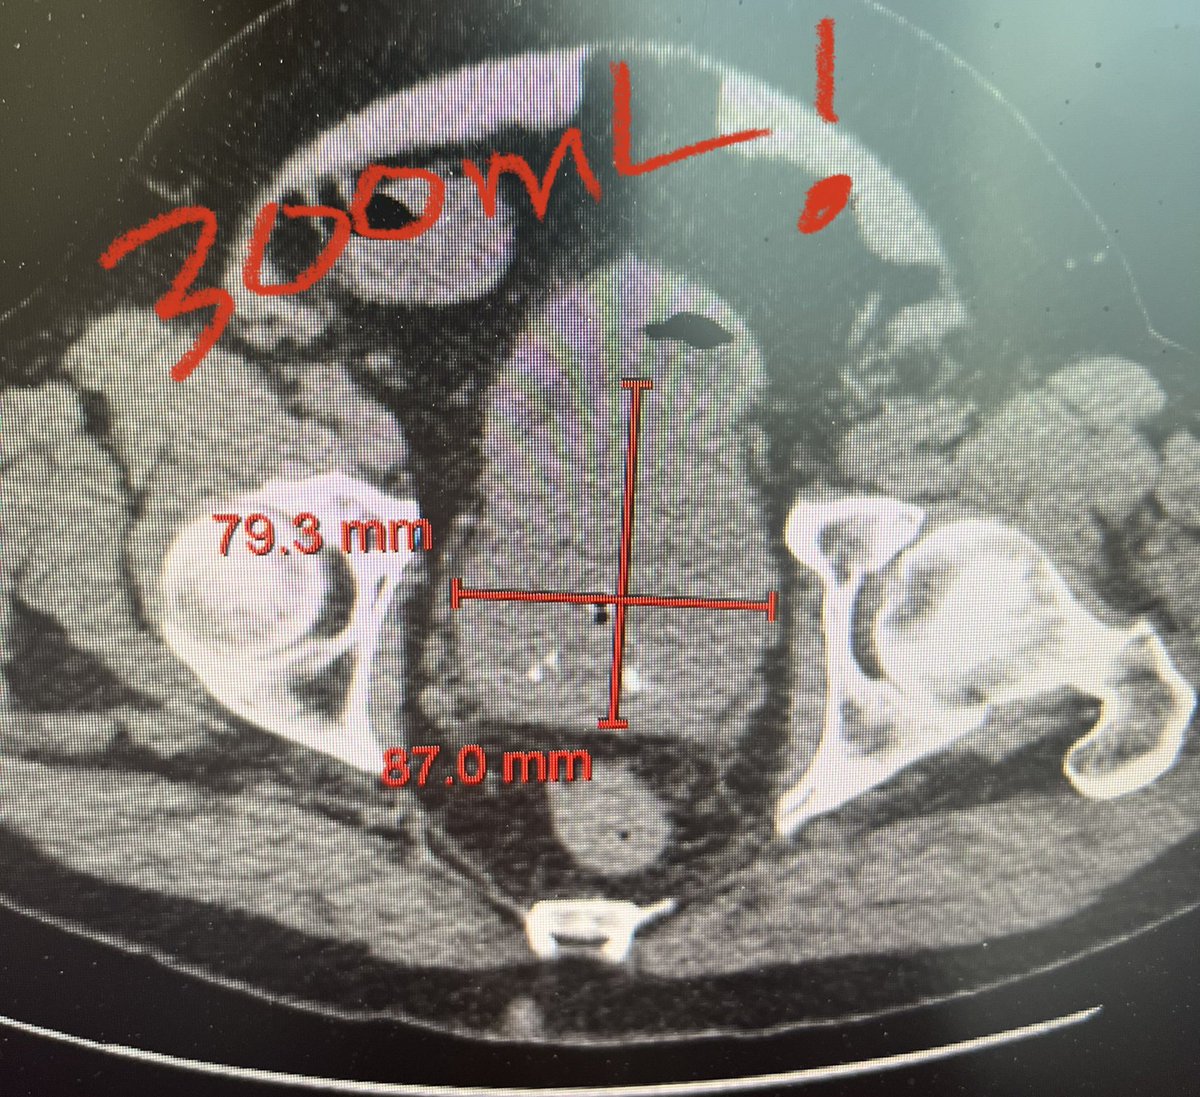

LEP program well on its way at Red Deer Regional hospital with 7th case completed this week. Collaborative provincial effort from U of A + U of C @AssmusMark @fadl_hamouche. Proud of Dr. Haines for first case front to back. Thanks @CanUrolAssoc and @Olympus_Corp for support